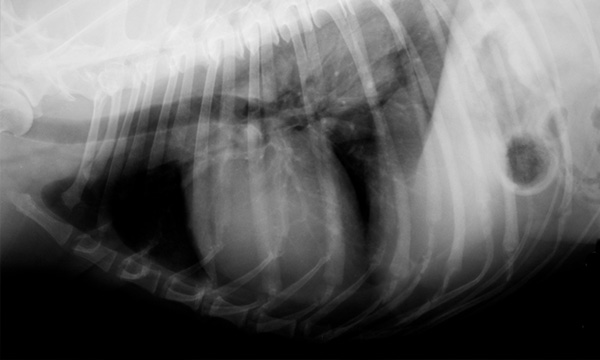

4レントゲン検査

心臓や肺、骨、内臓の大きさや形を調べ、異常がないか検査します。

ラブラドール・レトリバー/8歳/副腎腫瘍

普段はアトピー性皮膚炎で当院に通っている患者様です。

8歳になったのきっかけに健康診断実施したところ、お腹の中の副腎に腫瘍があることが健康診断でわかりました。

大学病院で検査をしてもらったところ、この子は無症候性の副腎腫瘍と診断されました。副腎腫瘍は大きくなると周囲の血管を巻き込み、手術の難易度が高くなります。

幸い、この子は早期に発見できたため、お薬による治療と、定期的に副腎のサイズを超音波検査することで落ち着きました。

今回の子のように症状がなくても体の中で進行していく病気はたくさんあります。

重症化する前に、定期的な検査により病気を見つけ、治療をしていくことが健康寿命の延伸に繋がります。